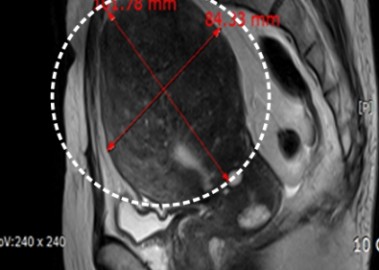

거대 자궁선근증 치료 사례